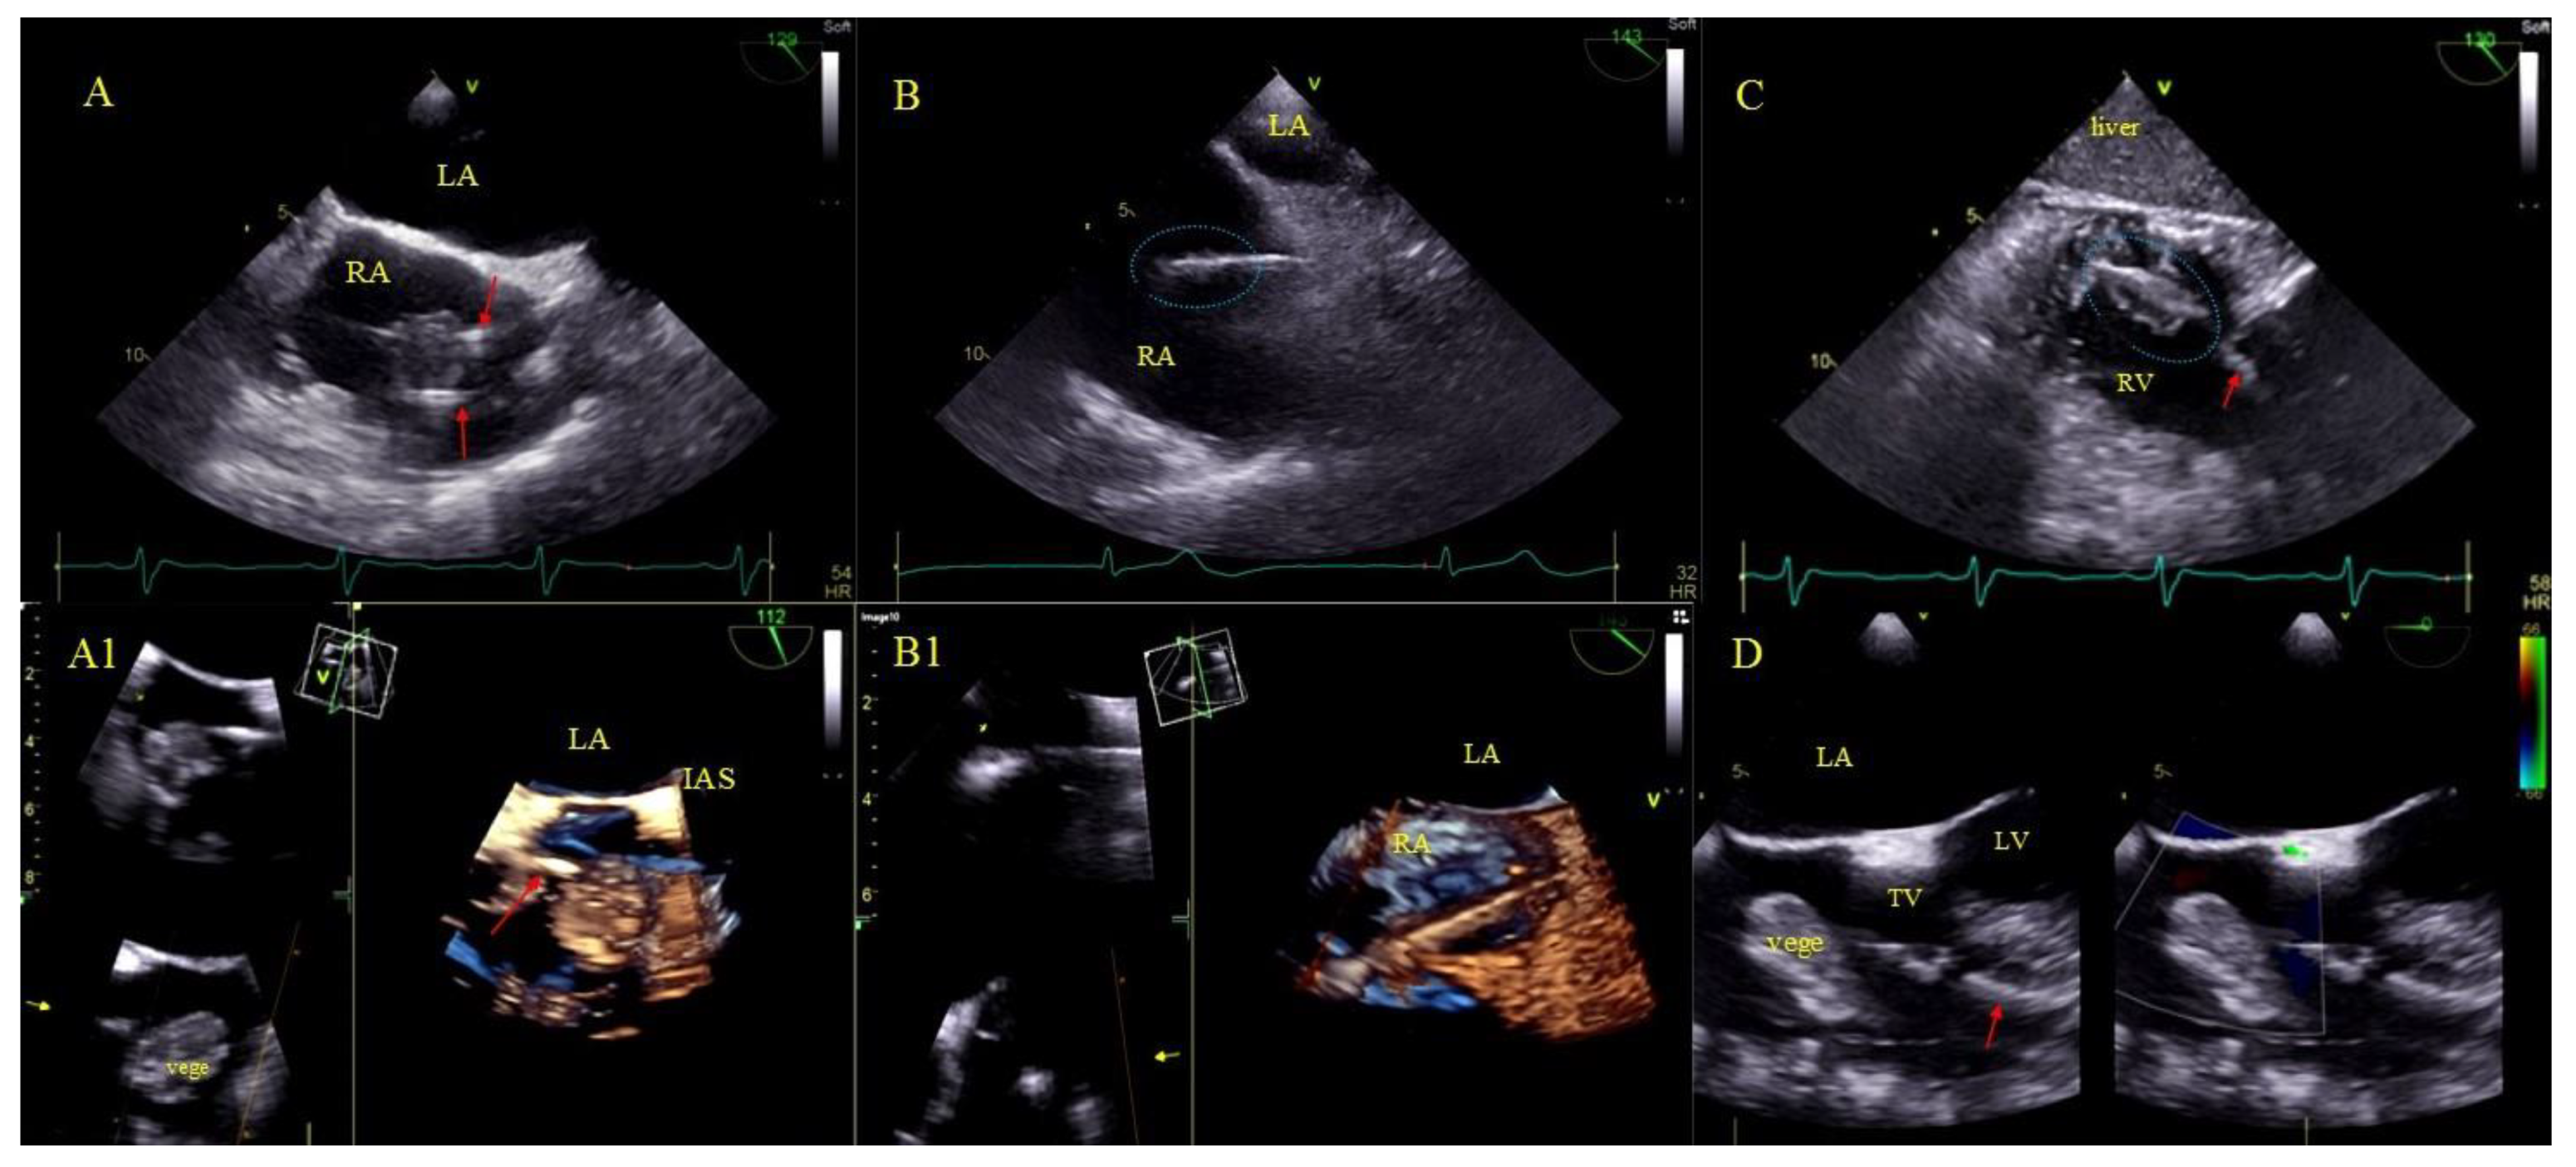

2.5. Echocardiographic Findings Associated with Endocardial Leads: Definition and Classification According to the Anatomy and Characteristic Features

- Non-modifiable factors related to the underlying disease (indication-dependent):Vegetations and LRIE have always been (in all previous analyses, including ours) one of the most potent factors decreasing chances of long-term survival [5,6,7,8,9,10,11,12,13,14,15,16,17,18,19,20,21,22]. Unfortunately, despite the improving standards [2,3,4] long-term mortality among patients after TLE performed due to LRIE does not improve as desired.

- Factors that have no effect on the procedure course and chances of long-term survival: AMEL (clots, vegetation-like masses) had no influence on chances of long-term survival in our analysis.